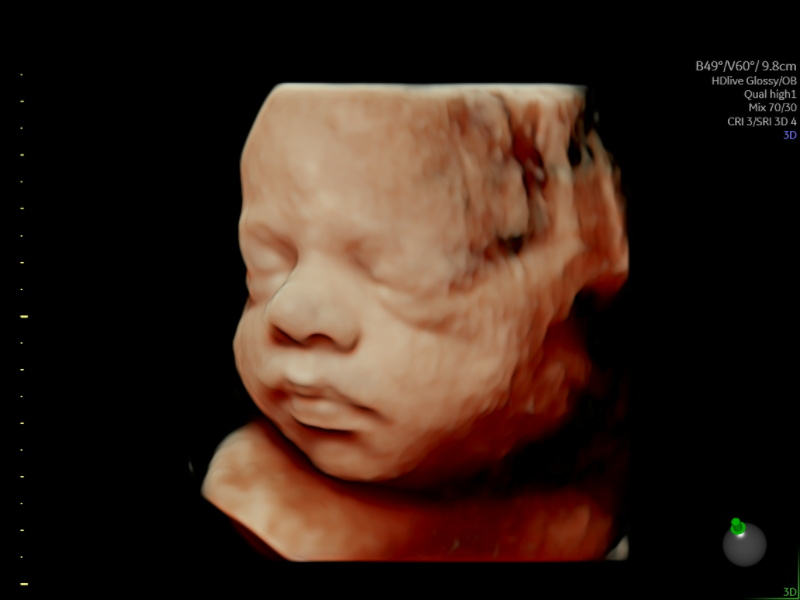

RealBaby™ Scan

Ireland's first RealBaby™ images - Turning 3D into RealBaby™ images for timeless keepsakes and a first true look at your baby.

Our state-of-the-art facility offers cutting-edge ultrasound technology, including Ireland's first RealBaby™ imaging service, ensuring that every detail is captured with unparalleled clarity.

HerView Premium 3D/4D/HD Pregnancy Scan

Gestation:22-34 Weeks

Capture breathtakingly realistic images of your baby with our HerView Premium 3D/4D/HD Pregnancy Scan scan. This specialised ultrasound experience goes beyond standard sonography, using advanced technology to create stunningly detailed 3D and 4D images and HD videos of your little one. Our clinical specialist sonographers will guide you through this unique bonding experience, allowing you to see your baby's facial features, movements, and even their tiny yawns. This is more than just an ultrasound; it's a chance to connect with your baby in a truly unforgettable way.